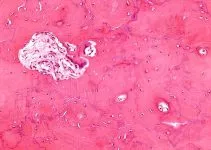

It is a condition that is characterized by a swelling of the bursa or the fluid-filled pouch located close to a joint at the lateral tip of the hip that is called the Greater Trochanter. This is the reason why Trochanteric Bursitis is often referred to as Greater Trochanteric Bursitis.

The condition leads to inflammation or irritation of the bursa, which commonly results in hip pain. The pain arises on the outer side of the thigh and hip or even in the buttock. The pain usually originates when the patient is lying on the impacted side.